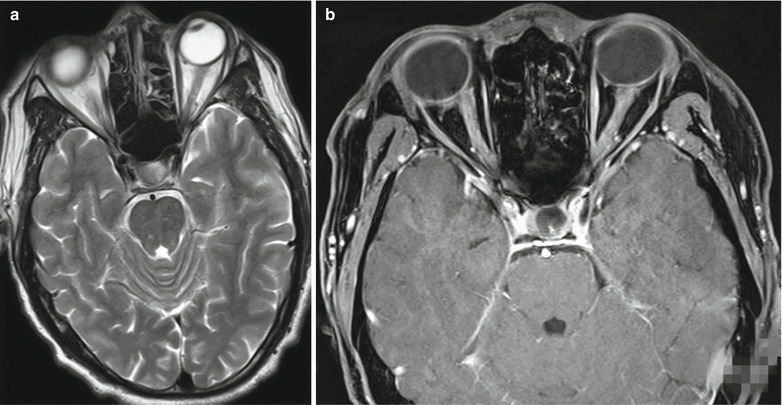

MR imaging demonstrates no abnormality at the early stage. However, several weeks later, MR imaging demonstrates mild atrophy of the cerebral cortex, hydrocephalus, and demyelination. The lesions are more commonly found at the white matters around the cerebral ventricles, the basal ganglia, the hippocampus, as well as subcortical and cerebellar white matters, with spots or flakes of long T1 long T2 signal and high FLAIR signal. The lesions are more favorably demonstrated by T2WI. DWI demonstrates limited perfusion. Enhanced imaging demonstrates enhancement of some lesions (Fig. 23.2).

Fig. 23.2.

Acute optic nerve encephalomyelitis. (a) Transverse MR imaging demonstrates multiple spots of long T2 signal at the brainstem. (b) Thickened bilateral optic nerves are demonstrated, with uneven enhancement. (c–f) Sagittal imaging demonstrates swelling of spinal cord at the level of C2–T11, with stripes of long T2 signal in the spinal cord. (g, h) Transverse imaging demonstrates long T2 signal in the spinal cord

In patients with spinal cord-related symptoms, MR imaging demonstrates spinal lesions in 80 % of the patients, which are focal or segmental. However, most cases are demonstrated with lesions in long spinal segment (above 3 vertebrae) or whole spinal cord.

The cases of measles complicated by optic neuritis are occasionally reported, with no specificity. Coronal T2WI demonstrates long T2 signal from the optic nerves. Contrast imaging demonstrates enhancement of the lesions, which is more commonly found at unilateral optic nerve.